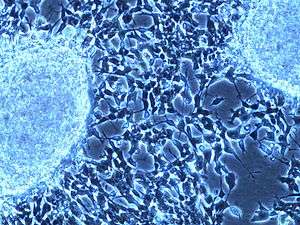

On microscopy, the tumor cells are typically described as small, round and blue, and rosette patterns (Homer Wright rosettes) may be seen. Homer Wright rosettes are tumor cells around the neuropil, not to be confused with pseudorosettes, which are tumor cells around a blood vessel.[25] They are also distinct from the pseudorosettes of an ependymoma which consist of tumor cells with glial fibrillary acidic protein (GFAP)–positive processes tapering off toward a blood vessel (thus a combination of the two).[26] A variety of immunohistochemical stains are used by pathologists to distinguish neuroblastomas from histological mimics, such as rhabdomyosarcoma, Ewing's sarcoma, lymphoma and Wilms' tumor.[27]

Neuroblastoma is one of the peripheral neuroblastic tumors (pNTs) that have similar origins and show a wide pattern of differentiation ranging from benign ganglioneuroma to stroma-rich ganglioneuroblastoma with neuroblastic cells intermixed or in nodules, to highly malignant neuroblastoma. This distinction in the pre-treatment tumor pathology is an important prognostic factor, along with age and mitosis-karyorrhexis index (MKI). This pathology classification system (the Shimada system) describes "favorable" and "unfavorable" tumors by the International Neuroblastoma Pathology Committee (INPC) which was established in 1999 and revised in 2003.[28]